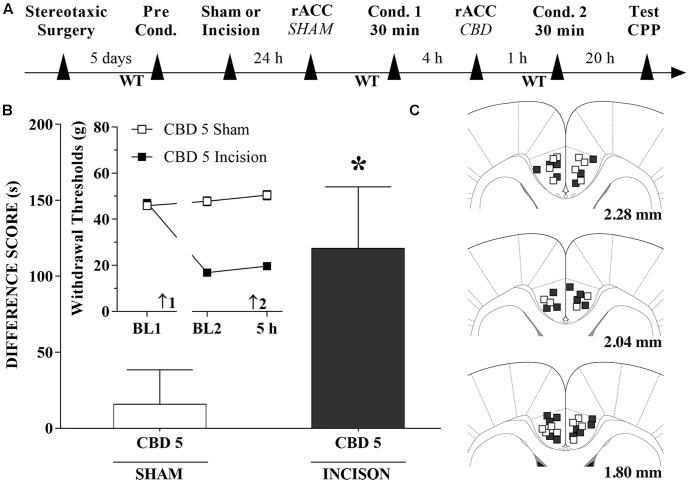

CBD Injections into the rACC Induce CPP

A timeline of the protocol for the experiments is shown in Figure 7A. CBD (5 nmol/0.25 μL), induced significant CPP in injured rats [t(20) = 2.1; p < 0.05] (Figure 7B). The insert shows that CBD (5 nmol/0.25 μL) injected into the rACC had no effect on WTs 1 h after injections. There was a significant effect of time [F(2,40) = 57.1; p < 0.01], treatment [F(1,20) = 293.6; p < 0.01] and interaction time × treatment [F(2,40) = 86.5 p < 0.01]. Figure 7C illustrates the microinjection sites in the rACC on diagrams of cross-sections from the atlas of ref. Paxinos and Watson (2006).